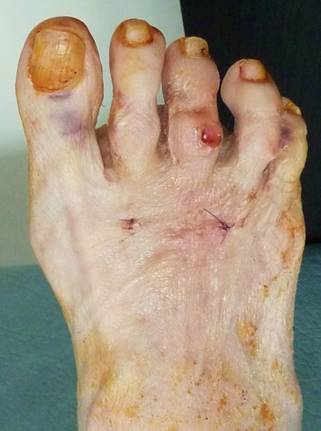

Палец приподнят над остальными за счет избыточного тыльного сгибания в плюснефаланговом суставе. Если уж думать о резекции, то о резекции основания основной фаланги, а не головки. Иначе основная фаланга так и останется приподнятой, а палец как мешал, так и будет мешать. Только станет короче и тугоподвижнее за счет фиксации спицей. После подобной операции палец вполне можно эффективно удерживать в нужном положении повязкой. А при необходимости положение пальца во время перевязки можно легко подкорректировать. Во вложенном файле пример возможности удержания пальцев повязкой в гораздо более серьезной ситуации.

Здесь стопа до и через неделю после вмешательства на первой перевязке. На операции были выполнены субкапитальные остеотомии 2-4 плюсневых костей, оснований основных фаланг 2-5 пальцев и средних фаланг 2-3 пальцев. И даже при таком объеме нужды в фиксации спицами нет.

Что видим: укорочение 2 плюсневой кости, лёгкую молоткообразную деформацию 2 пальца, незначительное варусное отклонение 3 пальца. И всё! Длина 1 пальца, длины всех остальных плюсневых костей симметричны (померяйте с линейкой физическую длину – она отличается в пределах 2 мм, т. е. в пределах погрешности измерения и рентгенологической позиции). Hallux valgus’а нет никакого, даже interphalangeus (посмотрите на другую стопу). Диагноз: брахиметатарзия 2 плюсневой кости. Соответственно, нужно эту самую кость удлинять. А не укорачивать (разворачивать, отклонять) соседние кости!!! Этими вмешательствами даже теоретически невозможно решить проблемы пациентки, а ведь у каждой операции есть последствия и риски.

Пациентку, скорее всего, беспокоит косметический дефект. И молоткообразная деформация 2 пальца - уже есть гиперкератоз на тыле проксимального межфалангового сустава. Варусное отклонение 3 пальца возникло компенсаторно, оно минимально и, скорее всего, пациентку не беспокоит.